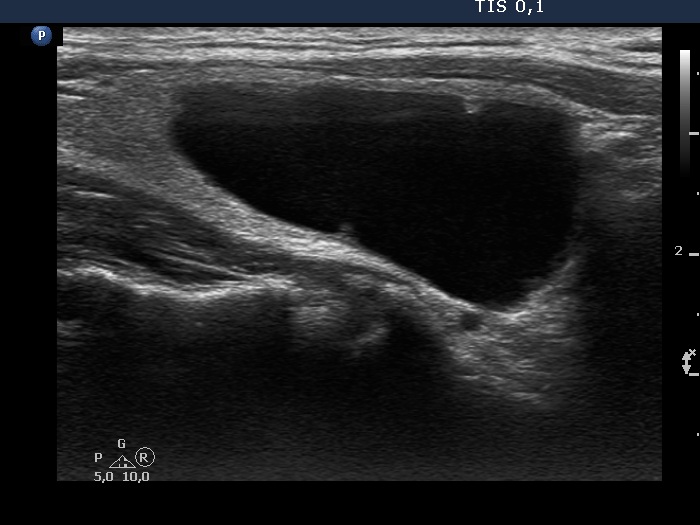

Present examination years after the first examination (third row of images)

Ultrasonography. Except for the size of the nodule, the pattern remained the same. The dimensions of the nodule were 23x15x33 mm - 5.95 mL.

At the first examination, the nodule compressed the vessels running outside the nodule while on follow-up this compression was released, therefore the perinodular vascularity became visible.

The nonparallel orientation became parallel.

- If we can remove only small proportion of cystic content, we usually offer a follow up within 6 months. In around third of cases, the thick content flows out and we can aspirate the cystic part.